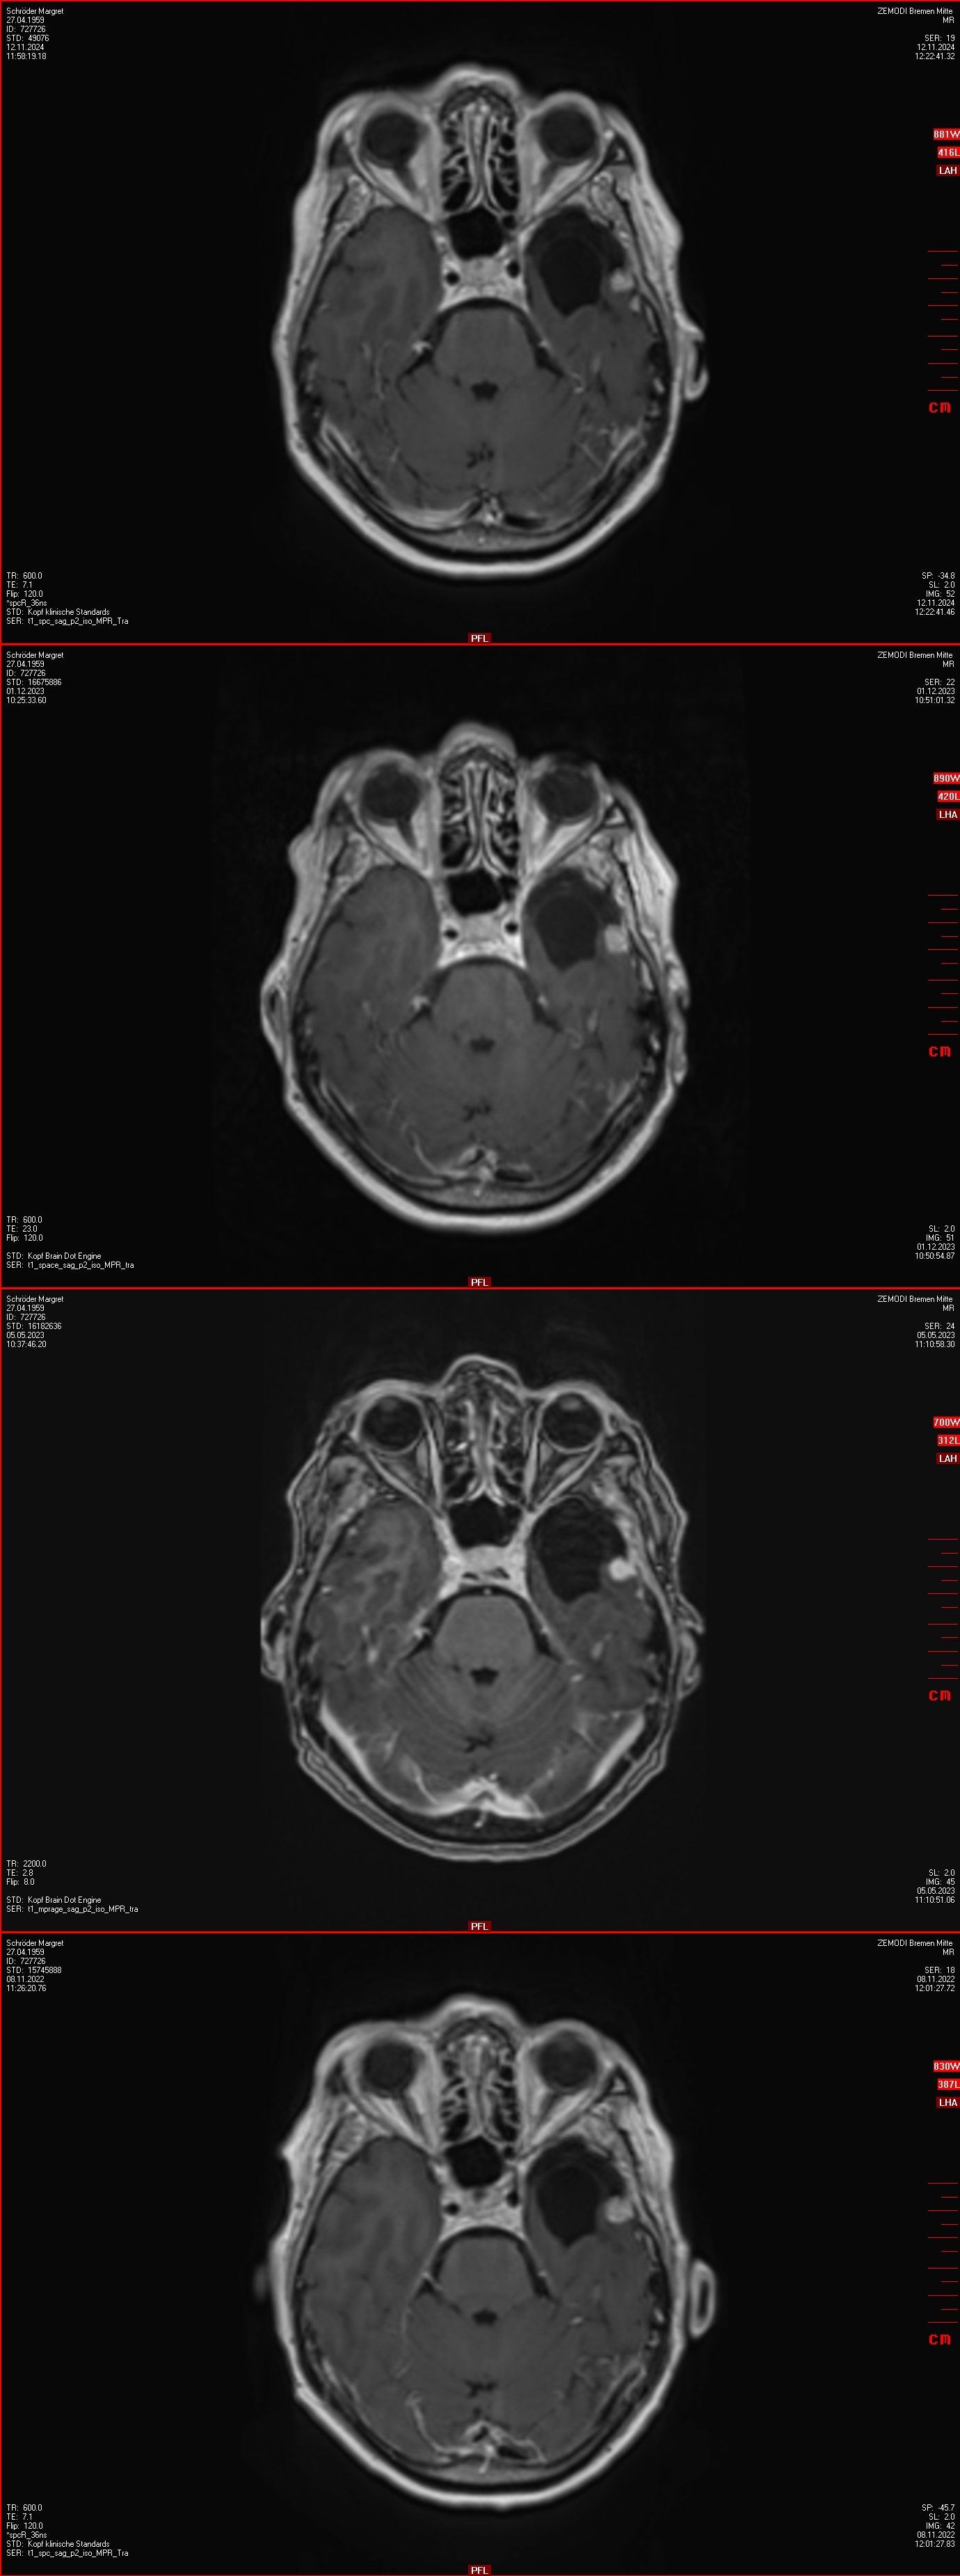

26.01.2021: Gamma-Knife

• GammaKnife-Behandlung eines kleinen links temporal duraständig gelegene Konvexitätsmeningeom (postoperatives Rezidiv)

13 x 9 x 10 mm,Volumen 0,53 cm3 , Minimumdosis 20 Gy.

April 2021 bis November 2024: Abwarten

Natürlich war ich regelmäßig beim MRT. Die Auswertungen wurden stets vom Radiologen und von einem Neurochirurgen im Bremen gemacht.

Schön zu sehen war, dass der bestrahlte Tumor kein Wachstum hatte - siehe Bilder vor dem Text.

12.11.2024: MRT

• unverändert zur Gamma Knife Behandlungssituation 2021 das kleine links temporale Konvexitätsmeningeom

• Ein progredientes links frontoorbitalis Meningeom (10 mm)

• Ein progredientes Meningeom links frontobasal en-Plaque wachsend mit Raumforderung am linken N.opticus mit Durchmesser 36x13x6mm

• Ein kleines Meningeom links temporamedial am Tentorium (9 mm),

• Ein weiteres sehr kleines links temporales Konvexitätsmeningeom (8 mm),

• Ein progredientes Meningeom links temporaparietaler Übergang (19 x 9 mm)